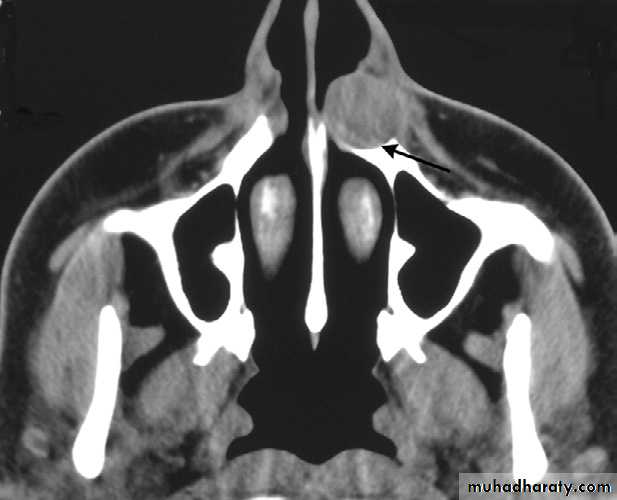

Nasolabial Cyst

The exact origin of nasolabial cysts is unknown. They may be fissural cysts arising from the epithelial rests in fusion lines of the globular, lateral nasal, and maxillary processes. Alternatively, the source of the epithelium may be from the embryonic nasolacrimal duct.

Location. Nasolabial cysts are primarily soft tissue lesions located adjacent to the alveolar process above the apices of the incisors. Because this is a soft tissue lesion, plain radiographs may not show any detectable changes. The investigation could include either CT imaging or magnetic resonance imaging, both of which can provide an image of soft tissues